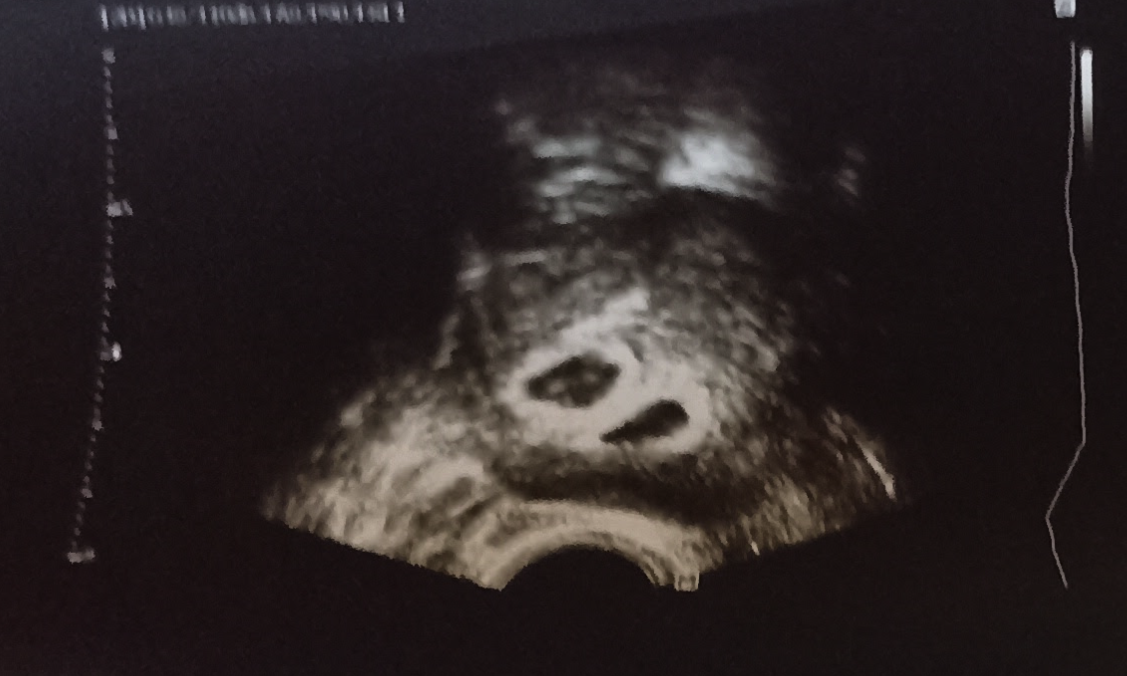

- понякога при извънматочна има псевдосак. Тук лекаря трябва да е достатъчно кадърен да пусне доплер, за да ги различи. Пуска се доплер и се вижда лесно дали е истински сак. И такова чудо си имах при извънматочната, визуализира се на един единствен преглед, след това пак го нямаше. НО ако лекар види нещо такова и каже "ето, има сак, всичко е ок", не се приема на сляпа вяра ако не е пуснал доплер. Ходи се след 2-3 дни пак на преглед:

Скрит текст: